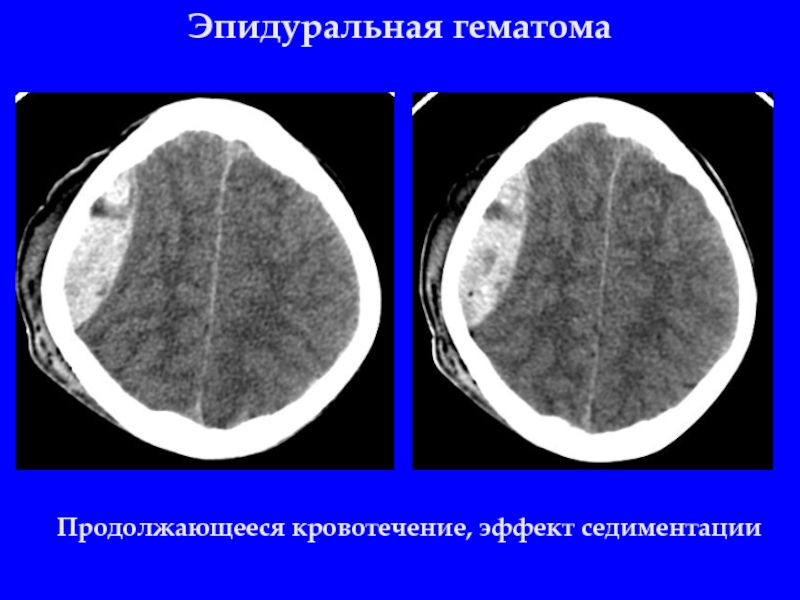

Слайд 10Эпидуральная гематома

Продолжающееся кровотечение, эффект седиментации